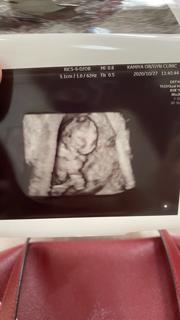

おててもあんよも見えた!かわいい!

足の間に見えるのは男の子のシンボルでしょうか?そんな早くみえませんよね??

2年前に子宮外妊娠からやっと授かりました(*´ω`*) 心臓も動いてて手と足も見えました\('ω')/ 先生からガリ股になってるって言われて笑ってしまいました(笑) 大きさは約2cm♪

左側が頭で、両手両足が見えました。 夫と、ダンスしてるみたいだね~と話してました(笑) つわりが辛く、家事がなかなか出来ません。 そろそろピークかな??ママ頑張ってるので、すくすく大きくなって下さい(^o^)